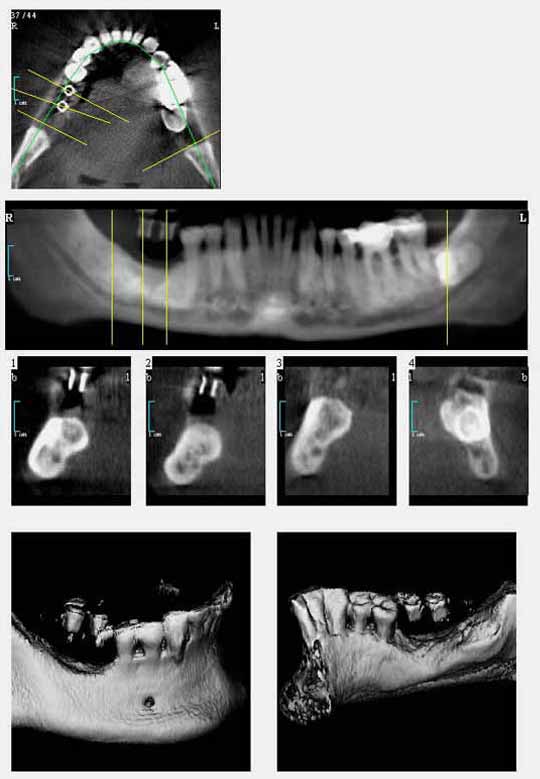

Der digitale Volumentomograph eröffnet für die Zahnheilkunde neue diagnostische Möglichkeiten. Wir setzen hier ein Gerät der Fa. Morita ein, das es ermöglicht auch kleine Aufnahmefelder (4*4 cm) zu tomographieren. Damit ist eine erhebliche Reduktion der Strahlenbelastung verbunden gegenüber Geräten, die nur große Aufnahmefelder untersuchen können. Wir nutzen diese Diagnostik für die Darstellung krankhafter Prozesse im Kiefer-Gesichtsbereich und für die Implantatplanung. Selbst für die Diagnostik vor Weisheitszahnentfernung kann eine solche Aufnahme sinnvoll sein, z.B. wenn die Gefahr einer besonderen Nervnähe besteht oder im Ramen einer Wurzelbehandlung wenn die Anatomie sich nicht durch zweidimensionale Aufnamen klären lässt.